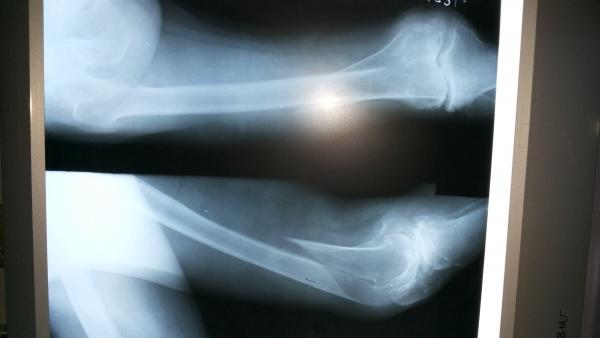

90岁股骨远端长螺旋形骨折

现病史:患者于1+小时前,在走路时不慎跌倒,左大腿部着地受伤,当时无昏迷、无呕吐、无抽搐及二便失禁,伤后感大腿部疼痛、活动受限,在外未经任何特殊处理,急来我院。X摄片示:左股骨远端螺旋形骨折,胸片、骨盆未见外伤性改变。

辅助检查:X片示:左股骨远端螺旋形骨折,胸片、骨盆未见外伤性改变,左膝关节退行性改变

初步诊断:1、左股骨远端螺旋形骨折 2、左胸壁挫伤 3、美尼尔氏综合症 4、双肾结石症5、左膝骨关节炎

3、术前、术中、术后特别需要注意的问题? 入院时正侧位

入院时侧位

入院时正位